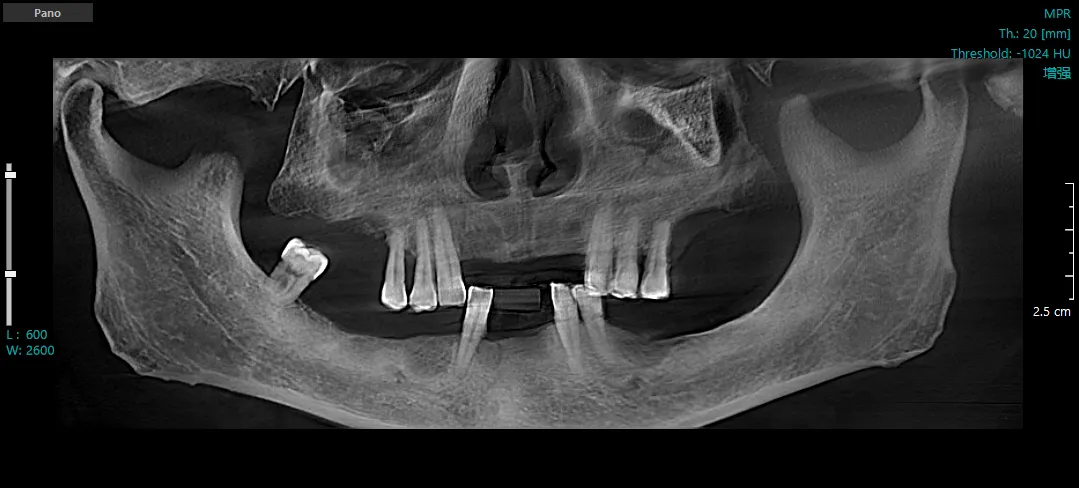

种植前CBCT三维重建图